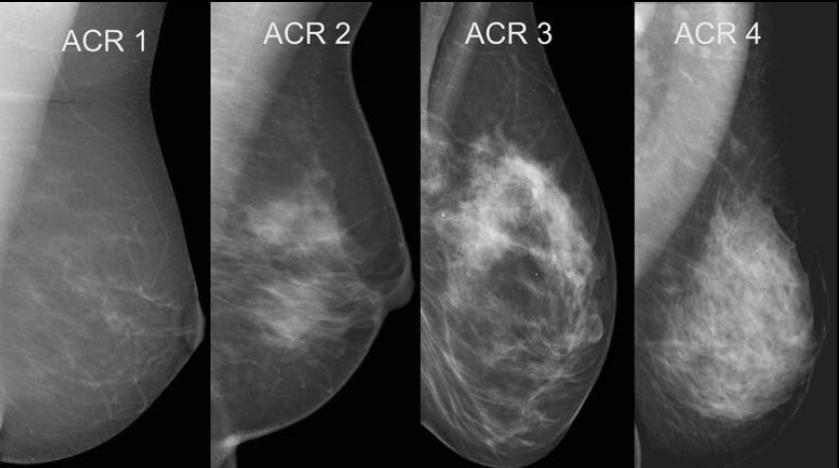

Algumas mulheres têm pouca gordura nas mamas e uma grande quantidade de tecidos glandulares e fibrosos. É o que os especialistas chamam de mamas densas.

Este é considerado um dos fatores de risco para o câncer de mama, já que essa característica aumenta em cinco vezes a probabilidade de desenvolver a doença.

Nesta imagem você pode ver a diferença entre mamas menos (à esquerda) e mais densas (à direita).

Além disso, alguns tipos de nódulos têm aspecto semelhante ao de tecidos normais de mamas mais densas, o que dificulta o diagnóstico por exames como a mamografia convencional.

Como a tomossíntese mamária “atravessa” a densidade das mamas com suas imagens extremamente finas, isso aumenta em até 30% as chances de se identificar tumores em mulheres com essa condição.